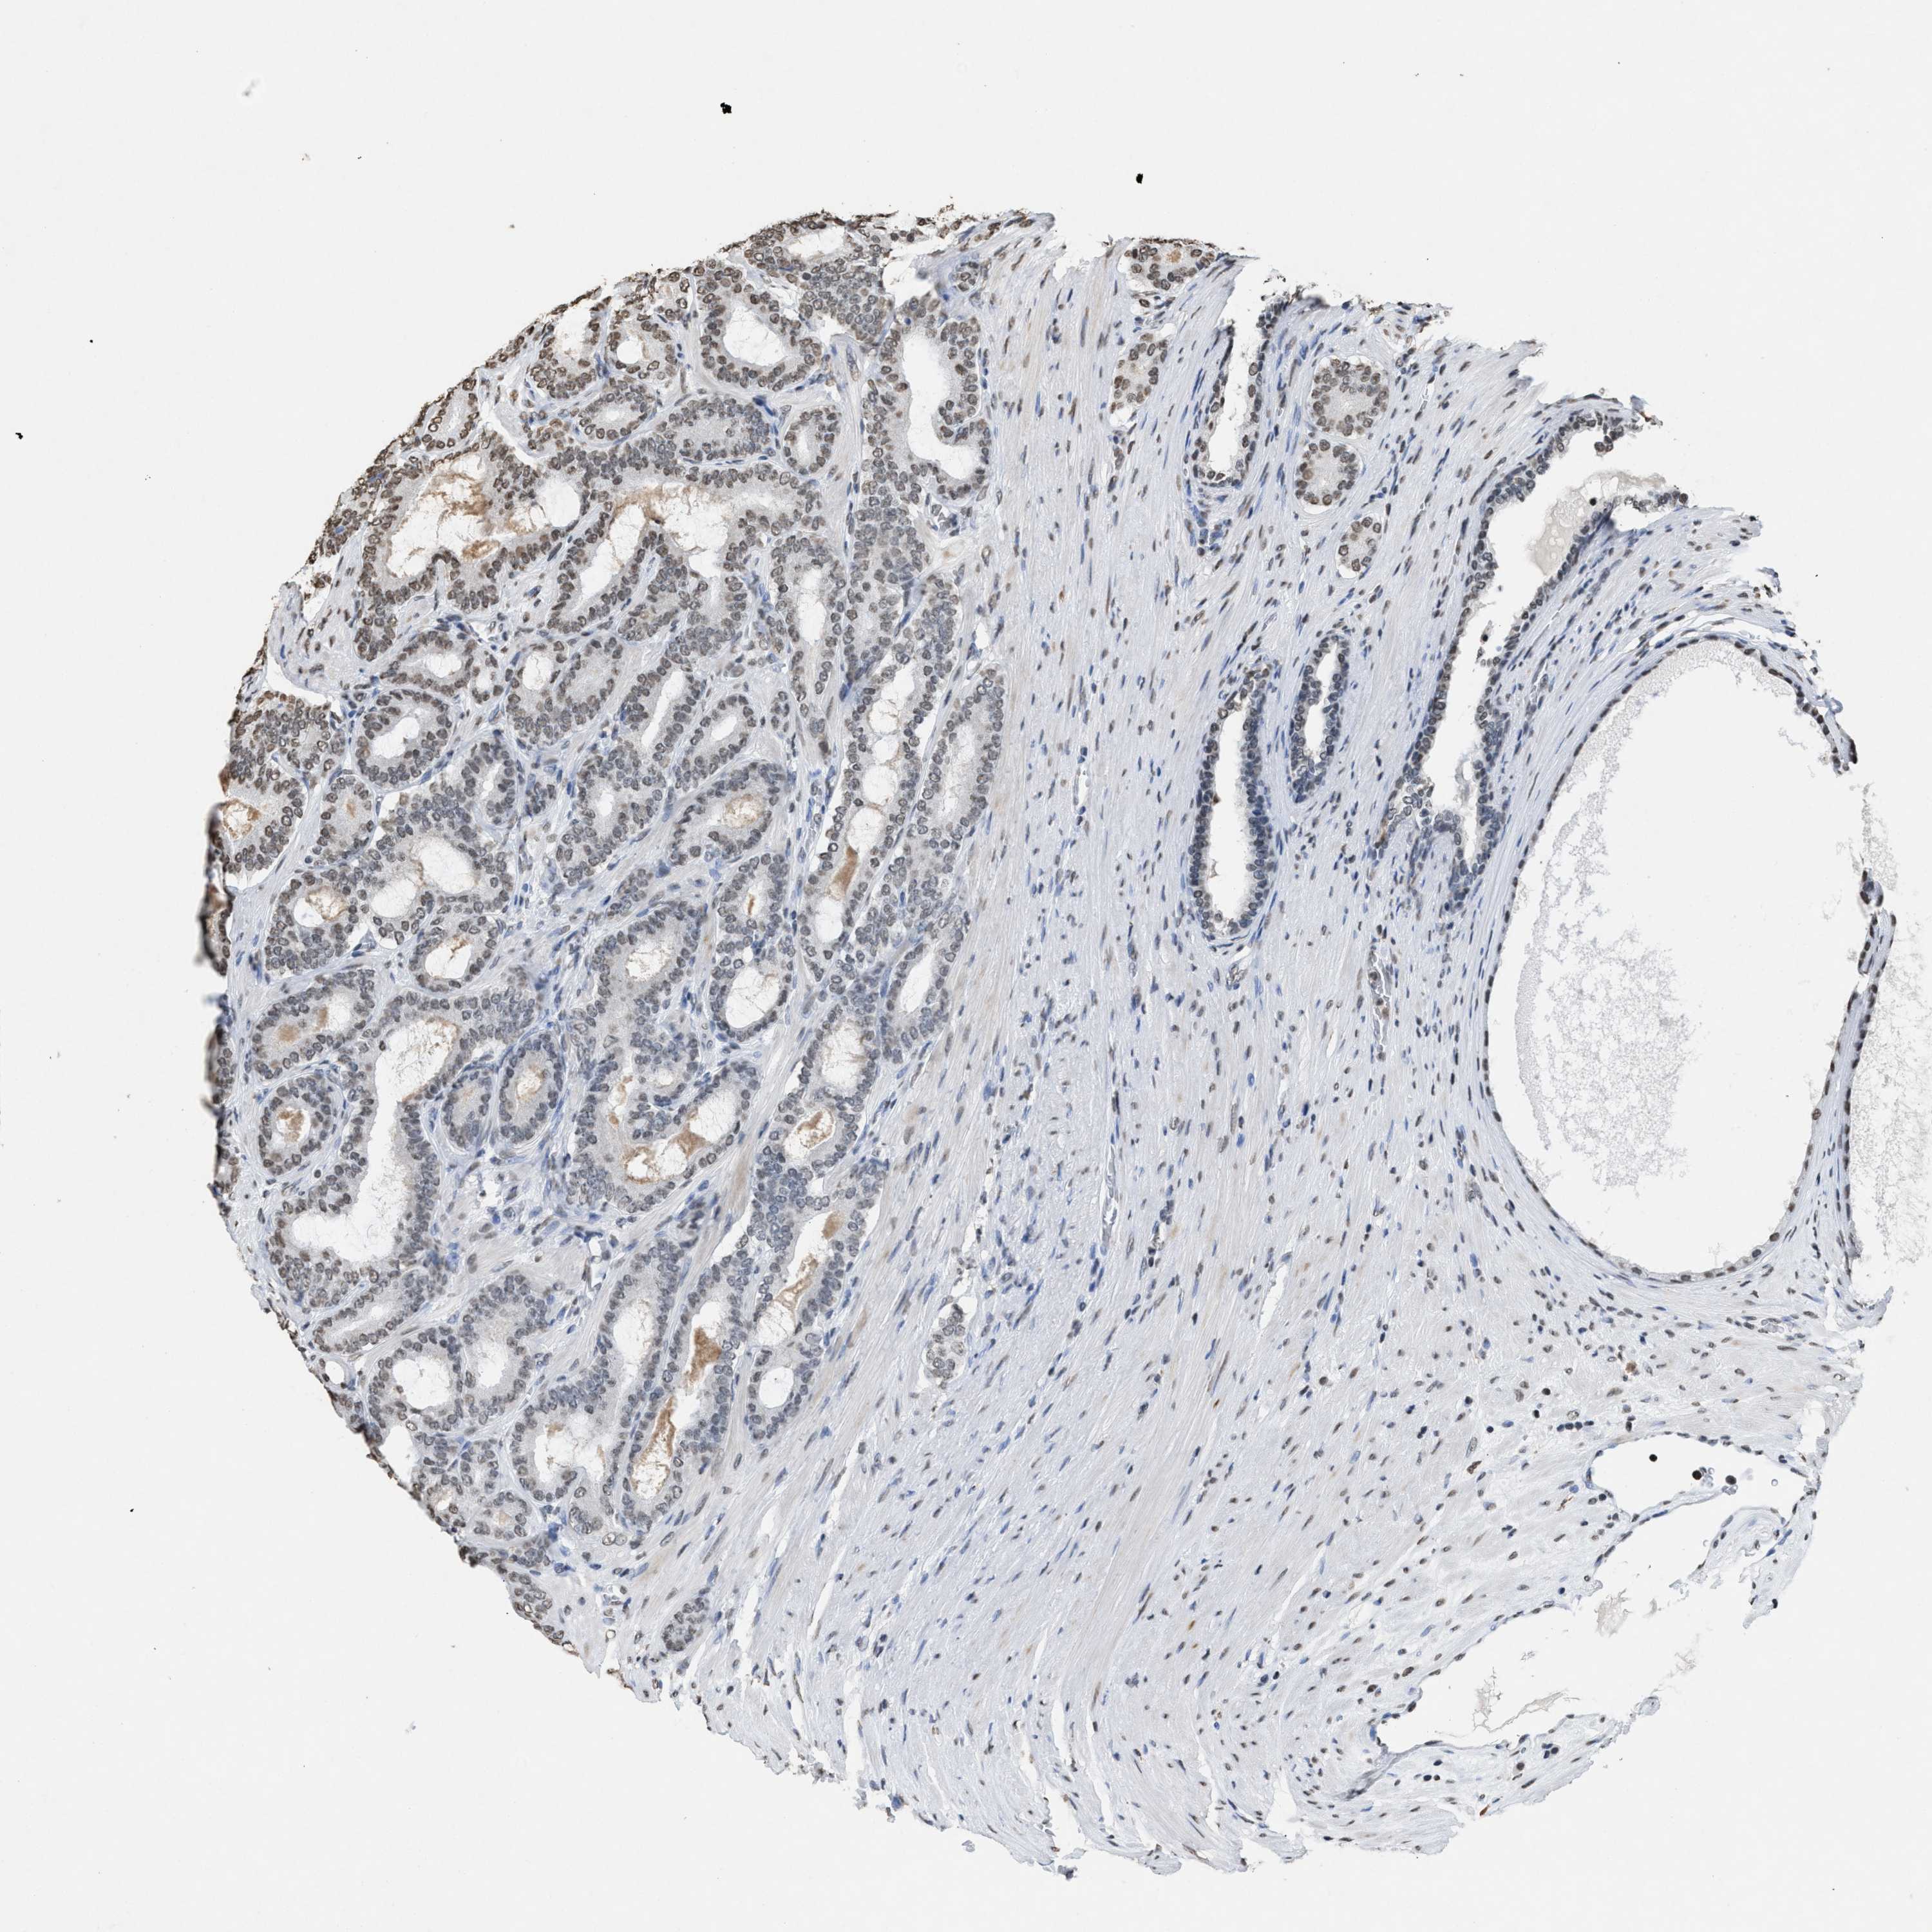

PROSTATE CANCER - Protein expressioni

A mouse-over function shows sample information and annotation data. Click on an image to view it in a full screen mode. Samples can be filtered based on level of antibody staining by selecting one or several of the following categories: high, medium, low and not detected. The assay and annotation is described here.

Note that samples used for immunohistochemistry by the Human Protein Atlas do not correspond to samples in the TCGA dataset.

Antibody stainingi

Antibody staining in the annotated cell types in the current human tissue is reported as not detected, low, medium, or high, based on conventional immunohistochemistry profiling in selected tissues. This score is based on the combination of the staining intensity and fraction of stained cells.

Each image is clickable and will lead to virtual microscopy that enables deeper exploration of all samples and also displays staining intensity scores, fraction scores and subcellular localization as well as patient and tissue information for each sample.

Antibody HPA021816

Antibody CAB002209

Staining

High

Medium

Low

Not detected

Intensity

Strong

Moderate

Weak

Negative

Quantity

>75%

75%-25%

<25%

None

Location

Nuclear

Cytoplasmic/membranous

Cytoplasmic/membranous,nuclear

Adenocarcinoma, High grade

Adenocarcinoma, Low grade

Adenocarcinoma, Medium grade